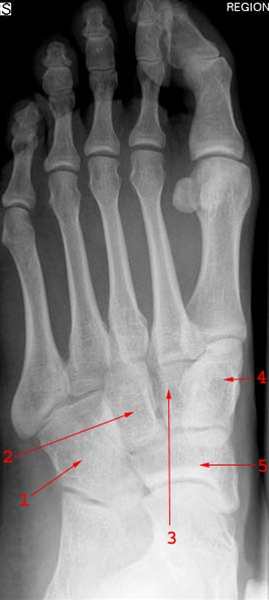

Fodrodsknogler, normal, skrå

1. Os cuboideum (terningbenet)

2. Os cuneiforme laterale (yderste kileben)

3. Os cuneiforme intermedium (mellemste kileben)

4. Os cuneiforme mediale (inderste kileben)

5. Os naviculare (bådbenet)